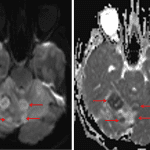

MRI

- Ill-defined T2/FLAIR hyperintense mass in the superior aspect of the right cerebellar hemisphere and superior aspect of the vermis measuring approximately 4.3 x 2.2 x 4.2 cm

- Nodular internal areas of restricted diffusion and corresponding patchy enhancement

- Peripheral susceptibility artifact about one of these nodular areas in the anterior aspect of the right cerebellar hemisphere, likely relating to hemorrhage

- Associated mass effect in the posterior fossa resulting in cerebellar tonsillar herniation and crowding of the fourth ventricle with mild obstructive hydrocephalus